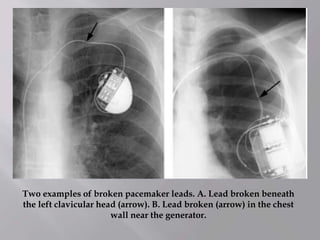

Two examples of broken pacemaker leads. A. Lead broken beneath

the left clavicular head (arrow). B. Lead broken (arrow) in the chest

wall near the generator.